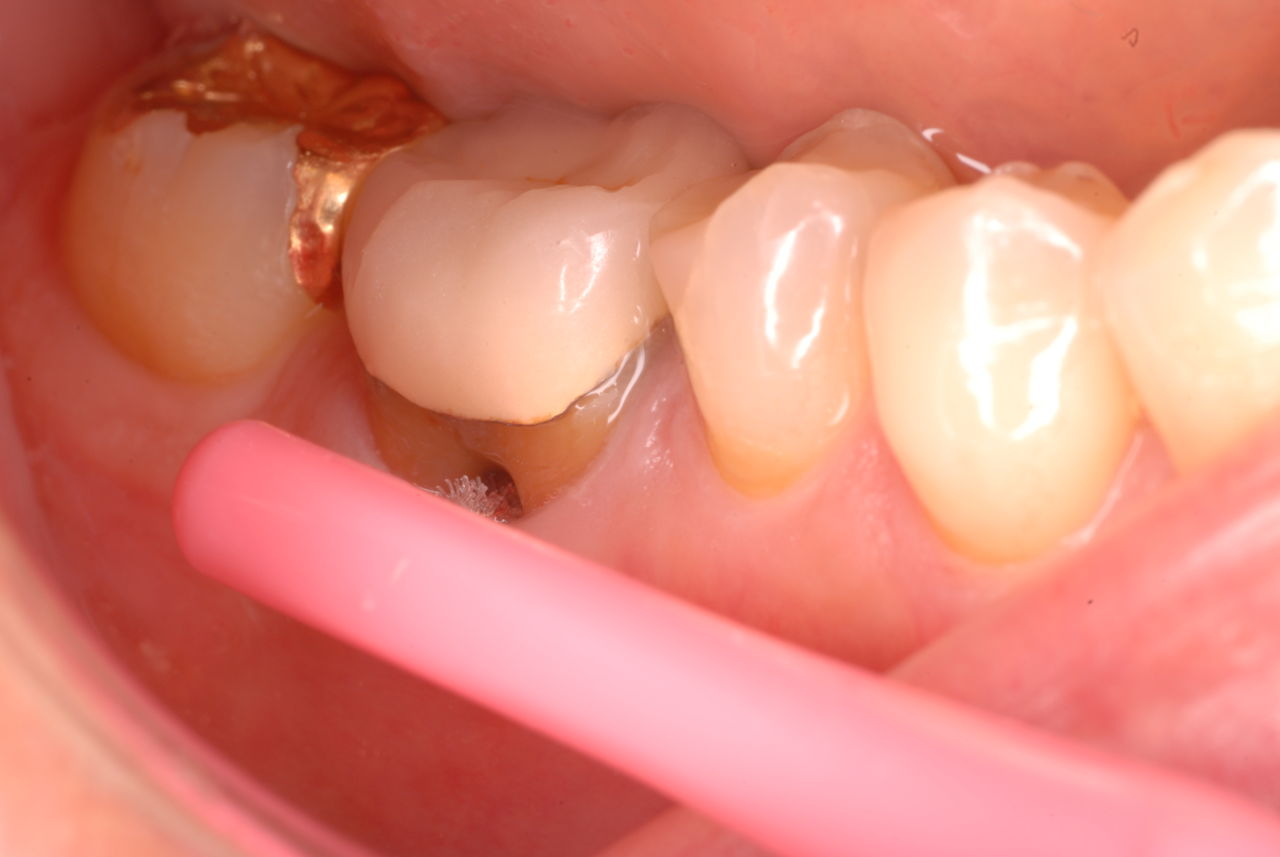

写真左下の親知らずが痛くなり抜歯しました。その後歯茎を除去して虫歯を露出させる処置を二回ほどしています。

レントゲンでは小さいですが、こう言う虫歯が一番怖いのです。

治療の成功率は極めて悪くすぐ再発しやすいのです。